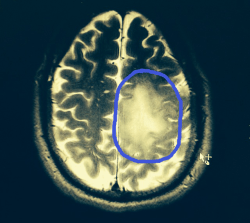

Brain Scan.. Not as pretty as my artwork…

I’m re-posting this for Ray. I have been following Ray for over a year now and was stunned when he shared this news. Let’s all go over to Etsy and buy a print….

So, here is a scan of my brain and the Tumor is circled. Its bigger than first thought. On the 9th I have one more MRI w/ spectroscopy to determine the rate of growth and cell types. Then it gets really hairy.

I am doing the best I can to be in good spirits and will continue to strive! It really helps knowing I have touched so many people with my artwork…